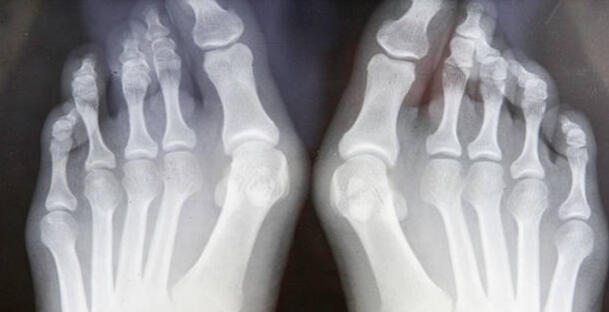

My Surgeon, Dr. Robert Juris, DPM, has performed well over 2,000 Lapiplasty Bunionectomy procedures.

lapiplasty bunion surgery